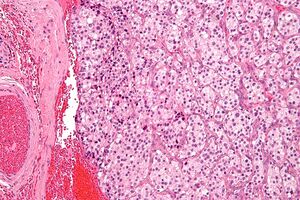

صورة مجهرية لورم في الجسم السباتي مع الزيلبالين المميزة . صبغة الهيماتوكسيلين واليوزين .

تظهر أورام المستقتمات بشكل كبير على شكل كتل سليلة الشكل متحددة بشدة ولديها اتساق مطاطي متماسك. وهي أورام وعائية شديدة وقد يكون لها لون أحمر غامق.[بحاجة لمصدر]

عند الفحص المجهري ، يتم التعرف على الخلايا السرطانية بسهولة. الخلايا السرطانية الفردية هي متعددة الأضلاع إلى بيضاوية ويتم ترتيبها في كرات خلوية مميزة تسمى زيلبالين.[7] يتم فصل كرات الخلايا هذه بواسطة سدى ليفي وعائي وتحيط بها الخلايا المعلقة .

عن طريق الفحص المجهري الضوئي ، يشمل التشخيص التفريقي أورام الغدد الصم العصبية ذات الصلة ، مثل الورم السرطاوي ، وسرطان الغدد الصم العصبية ، و سرطان الغدة الدرقية النخاعي

بواسطة كيمياء الأنسجة المناعية ، تكون الخلايا الرئيسية الموجودة في كرات الخلية موجبة للكروموجرانين ، سينابتوفيزين ، إنولاز محدد الخلايا العصبية ،سروتونين ، الخيوط العصبية و جزيء التصاق الخلايا العصبية ؛ هم بروتين S-100 سلبي. الخلايا المعلقة هي S-100 موجبة وإيجابية بؤريًا للحمض البروتيني الدبقي الليفي . عن طريق الكيمياء النسيجية ، تكون خلايا ورم المستقتمات عبارة عن خلايا أليفة الفضة ، وسلبية لحمض الشيف الدوري ، و سلبية لمليوسيكارمين ، و سلبية لأليف الفضة.[بحاجة لمصدر]